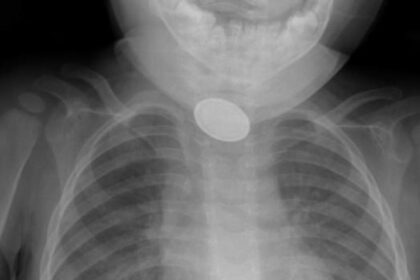

Kayseri’de 15 aylık bebeğin yemek borusuna pil ve lego oyuncak parçası kaçtı. Cisimler, bebeğin nefes borusundan 3 saatlik operasyonla çıkarıldı....